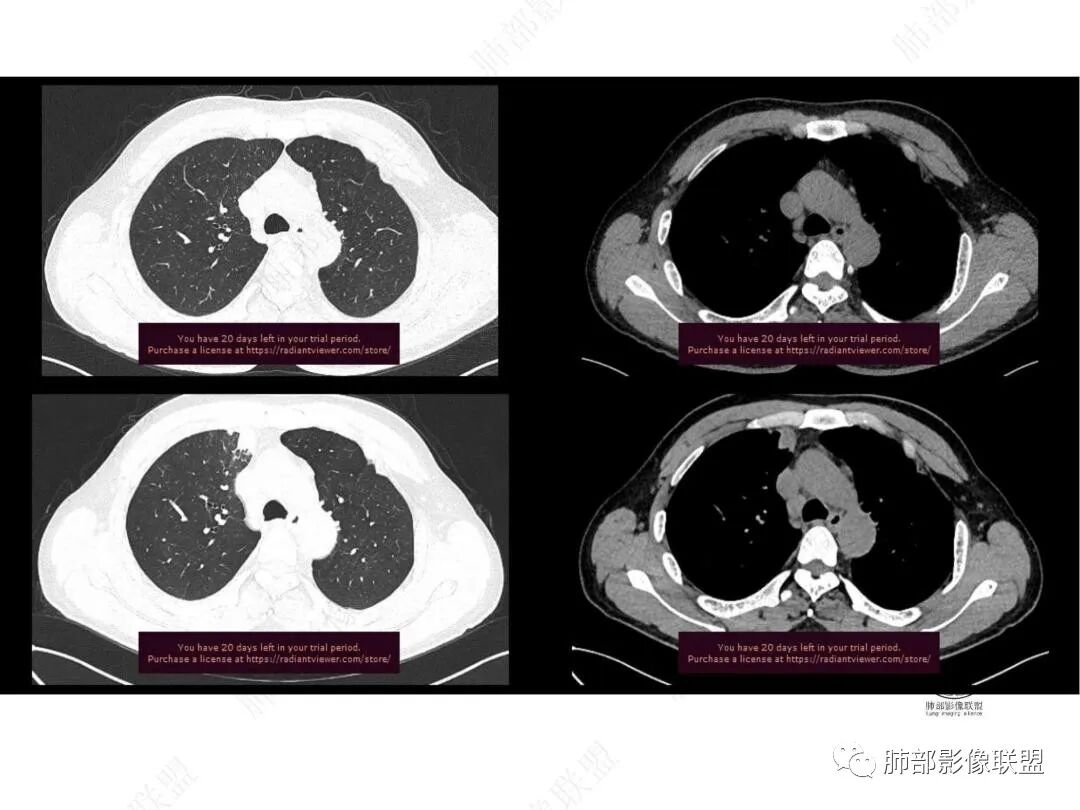

平扫图像

增强图像

右上叶前段胸膜下新发病灶;纵隔淋巴结较前增大

边缘平直,有锯齿状影

支气管进入其中,中近端堵

远端见斑片状高密度影

强化与肌肉类似,纵隔淋巴结强化类似

与胸膜关系:糊墙

1.中年男性,临床发热,症状较轻,中长病程,炎性指标轻度增高。

2.右肺上叶纵隔旁新发实性密度病灶,密度均匀,轻度强化,未见空洞、液化坏死及钙化,血管穿行自如,支气管进入后狭窄截止。灶周磨玻璃影边界不清,病灶未见明显分叶毛刺,平直、轻度收缩、周围偶见结节影,但未见树芽征。注意纵隔胸膜侵入或突入比较明确。纵隔淋巴结轻度增大。